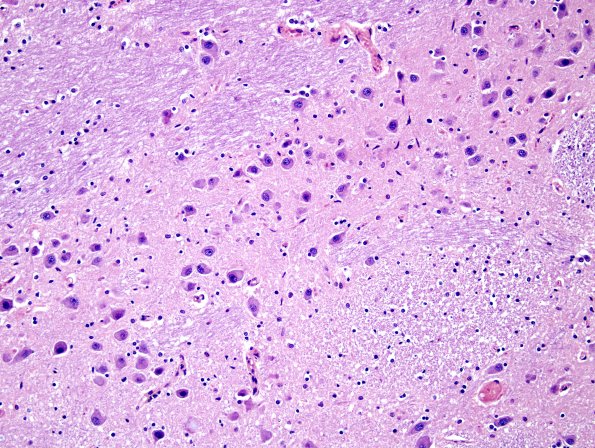

The basis pontis in a normal adult demonstrating pontine nuclei, transverse and descending tracts at several descending tracts. (H&E)